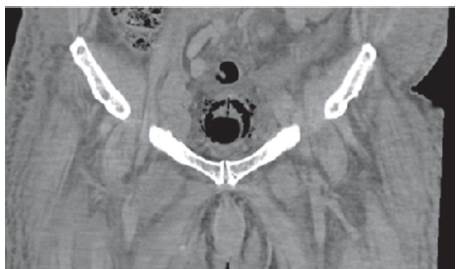

Se recibe reporte de patología, el cual evidencia tumor neuroendocrino tipo células de Merckel; entonces se valora por Oncología, donde indican inicio de quimioterapia ambulatoria, una vez se dé el egreso hospitalario. Una semana después el paciente presenta hematuria franca y oliguria; en estudios de laboratorios evidencian uroanálisis con hematuria, proteinuria en rango nefrótico y sedimento activo, con función renal dentro de parámetros de normalidad. Dados los nuevos hallazgos clínicos y el antecedente de diabetes, se decide solicitar estudios adicionales, descartando por oftalmología retinopatía diabética; adicionalmente el equipo de Nefrología descarta síndrome nefrótico, al evidenciar orina de 0,3 g en 24 horas, hipoalbuminemia y perfil lipídico normal; así mismo la morfología globular se encontraba en el 60% de hematíes eumorfos, descartando glomerulopatías. Investigando el origen de la hematuria, se complementa con estudios anatómicos; en efecto, se inicia con ecografía de vías urinarias que reportan buena diferenciación cortico-medular con riñones conservados de tamaño; posteriormente se solicita UROTAC para observar el tracto urinario bajo, evidenciándose engrosamiento de la pared vesical, gas perivesical como se observa en las imágenes 1, 2 y 3, y con conglomerados ganglionares retroperitoneales, hallazgos compatibles con cistitis enfisematosa.

Dado el hallazgo anterior se solicita urocultivo y baciloscopia en orina para determinar la etiología, y adicionalmente se pide valoración por urología, descartando indicación de manejo quirúrgico. Las baciloscopias seriadas de orina son negativas y en el urocultivo se aisla E. coli patrón BLEE; se indicó continuar manejo antibiótico con ertapenem por 14 días y seguir con sonda vesical; posteriormente cesa hematuria macroscópica y aumento el gasto urinario. En relación con conglomerados ganglionares descritos, se planteó posible compromiso tumoral para posterior seguimiento de forma ambulatoria con servicio de oncología. Ver cuadro paraclínicos.

Para el diagnóstico de la CE y para descartar diagnósticos diferenciales como fístula vésicocólica, abscesos intraabdominales, neoplasias adyacentes y pielonefritis enfisematosa, se hace necesario el uso de métodos imagenológicos como la radiografía abdominal convencional simple, la ecografía abdominal y la tomografía computarizada, donde pueda ser evidenciado el gas en la vejiga, el engrosamiento de las paredes vesicales9.

El caso aquí reportado se correlaciona con lo encontrado en la literatura desde el punto de vista del aislamiento microbiológico que corresponde a una Escherichia coli, aunque el nuestro es una E. Coli con patrón de resistencia a betalactamasas de espectro extendido (BLEE), probablemente por las complicaciones anotadas, como la hospitalización previa para el manejo posoperatorio del colgajo de piel y el uso de antibióticos en dicha hospitalización. También, se correlaciona con la literatura en la presentación del cuadro clínico, el antecedente de diabetes como el factor de riesgo más asociado, y en el abordaje diagnóstico, en el cual se pudo documentar el aire perivesical por medio del UROTAC, que es el examen con mayor sensibilidad y especificidad para el diagnóstico de esta patología.